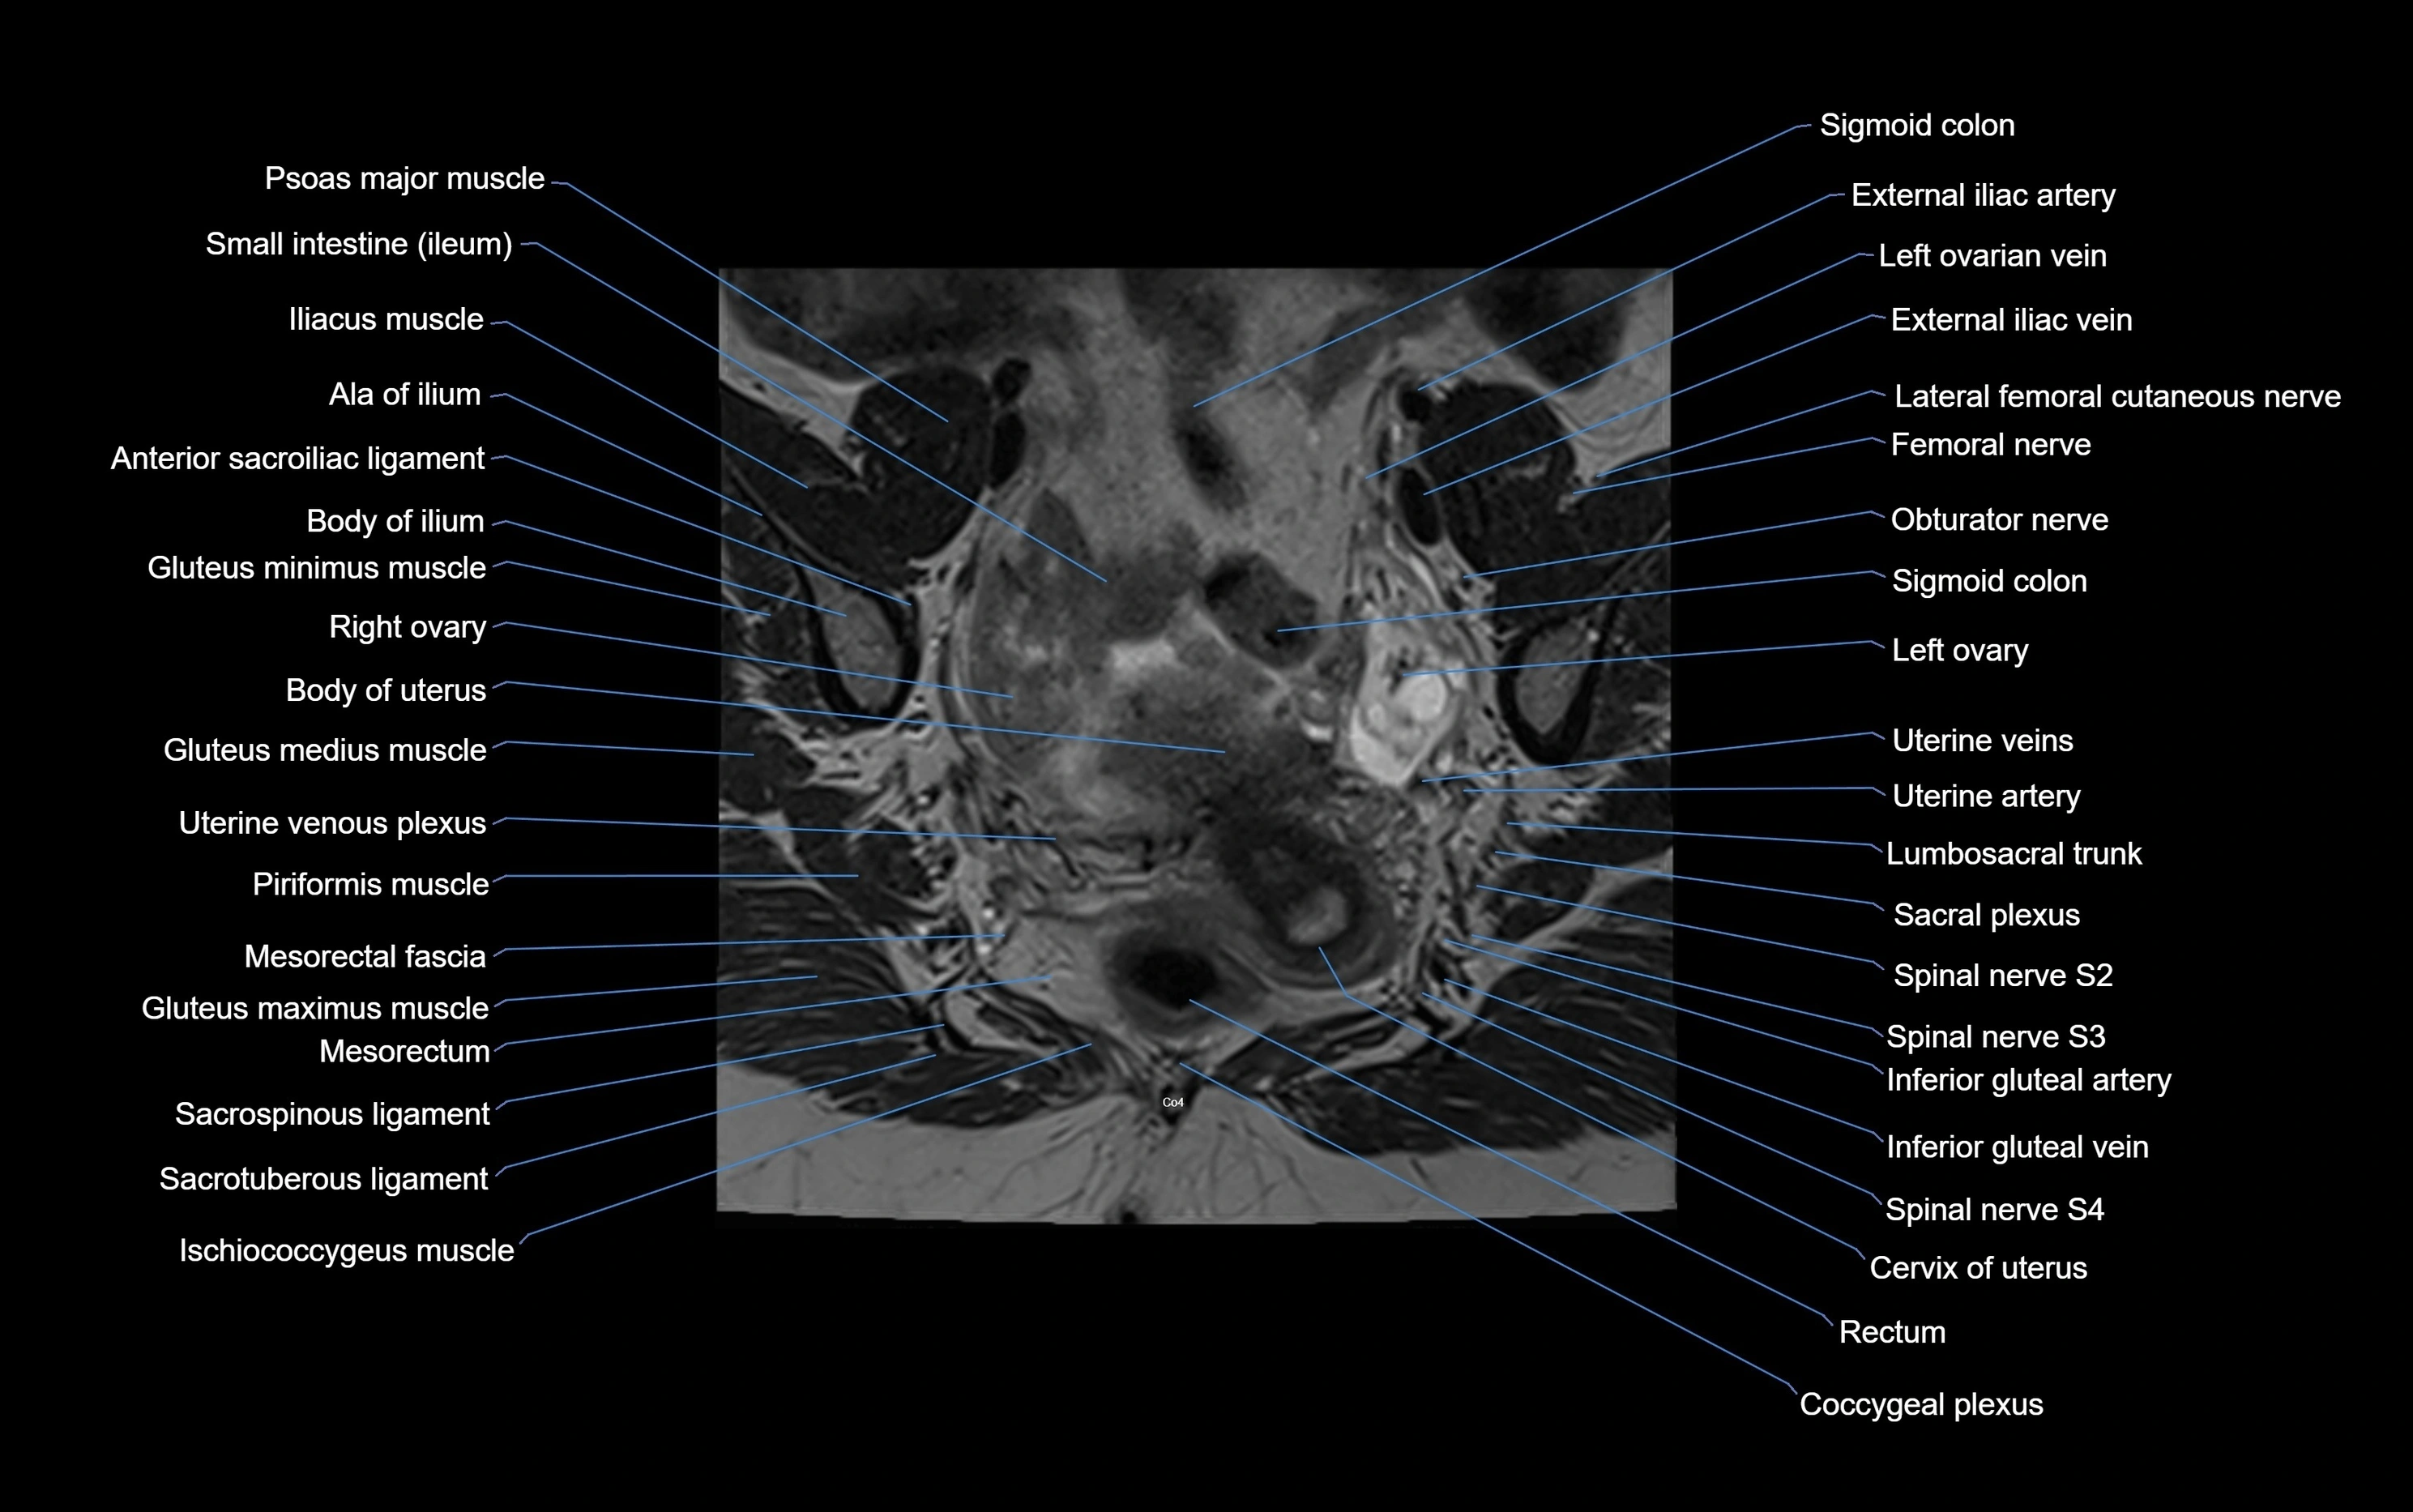

MRI image

image